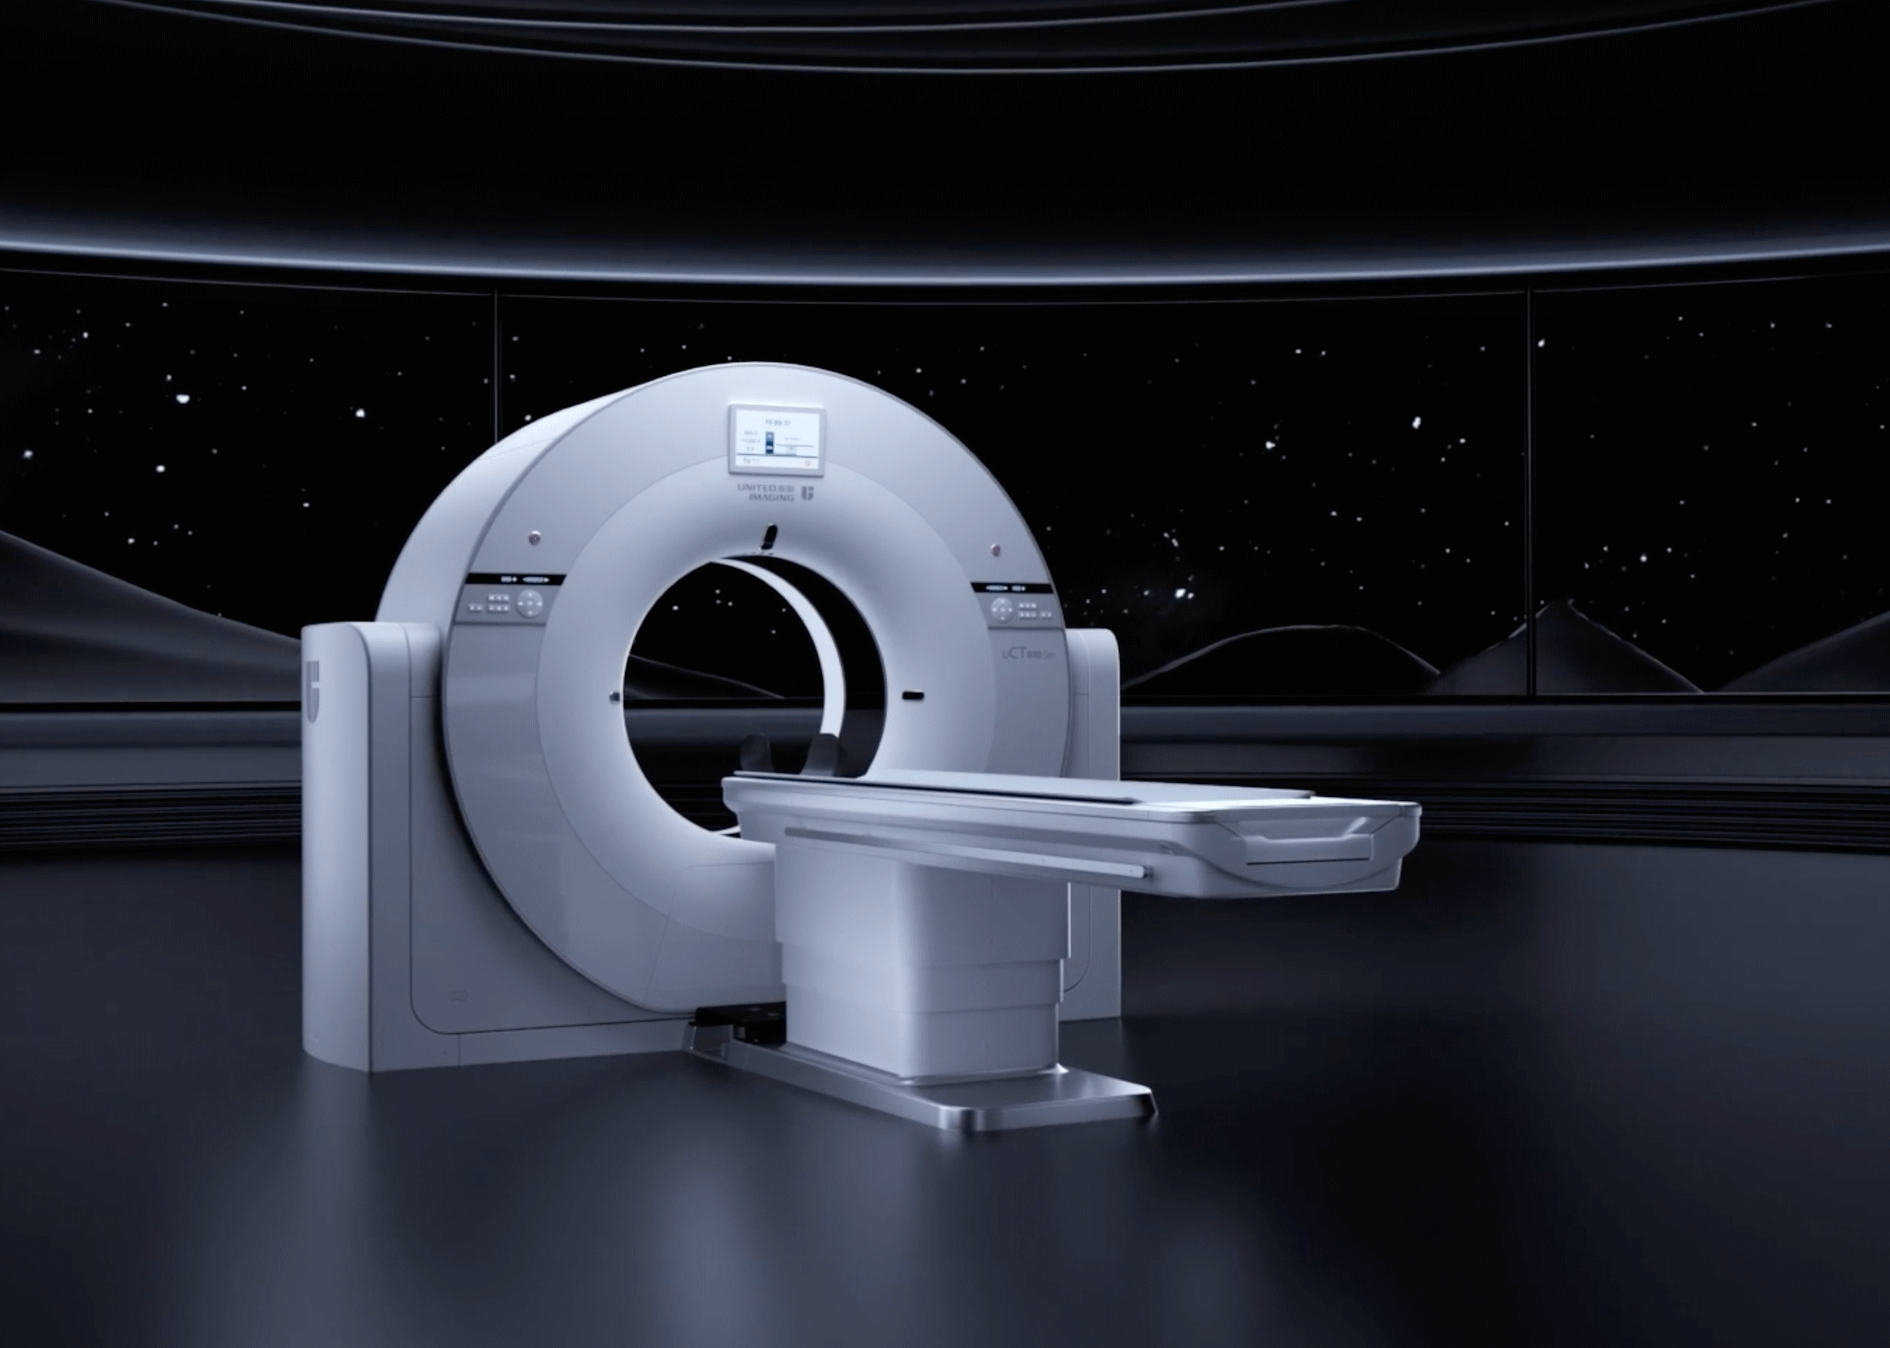

有容乃大

全视野自由成像空间

提供充足的患者摆位空间,支持放疗场景下容纳各类大尺寸定位附件;为介入影像引导手术提供更自如的操作空间

相较于常规CT系统,扫描视野提升26%*,对大体重、偏中心摆位等特殊患者模拟定位扫描呈现更加完整的解剖结构

*相较于70cm孔径CT系统

基于深度学习神经网络充分优化扩展视野部分“环形带”投影,有效消除截断伪影,大幅提升全视野成像质量和定量准确性